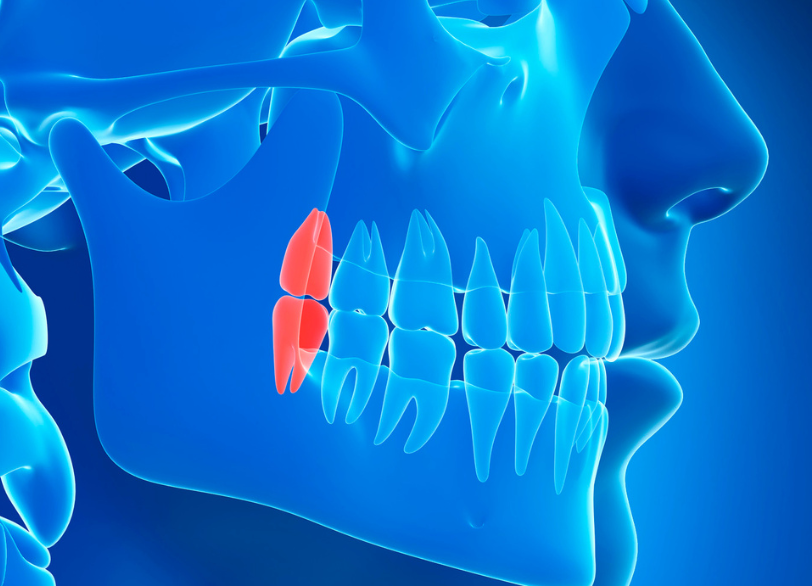

歯科用CTによる、三次元での徹底分析

特に下の親知らずの抜歯において最も注意しなくてはならないのがすぐ近くを走行している「下歯槽神経(かしそうしんけい)」という太い神経との位置関係です。

従来の二次元的なレントゲン写真だけではこの神経と歯の根との正確な距離や位置関係を把握することは困難でした。

当院では必ず歯科用CTによる撮影を行います。

CTを用いることで歯の根の複雑な形や神経管との立体的な位置関係を0.1ミリ単位であらゆる角度から正確に把握することができます。

これにより術中に神経を傷つけてしまうといった偶発症のリスクを限りなくゼロに近づけることが可能になります。

この術前の「見える化」こそが安全な抜歯の絶対的な土台となるのです。